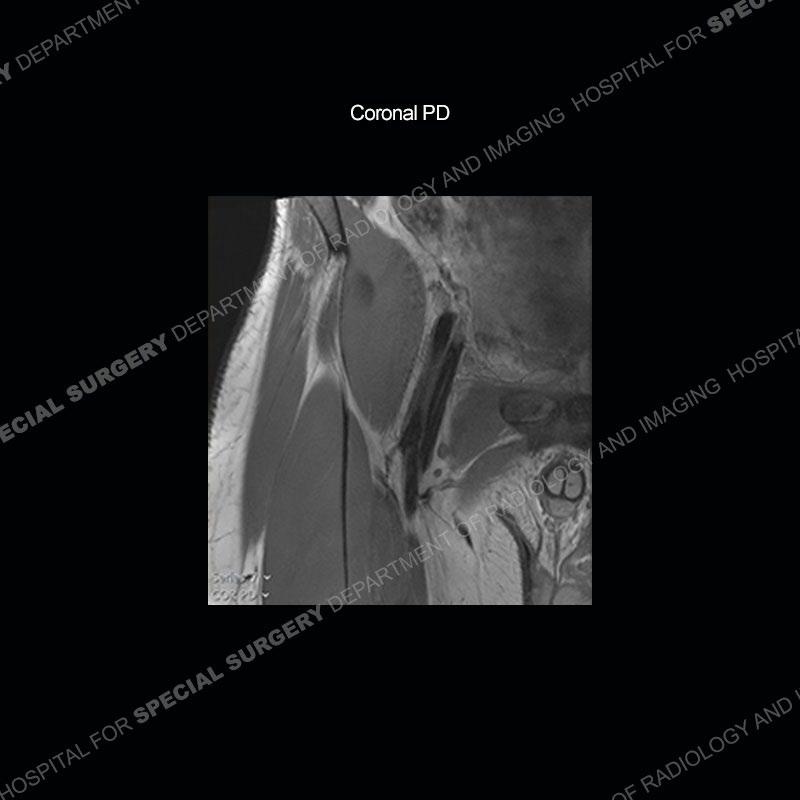

Radiographs did not demonstrate any clear abnormality. The MRI shows markedly abnormal signal of the right superior pubic ramus and abnormal signal/”mass” extending into the adjacent soft tissue. The inferior articular surface of the ramus showed what was thought to be bony destruction. CT examination shows a destructive process of the right superior pubic ramus.

Subsequent MRI in a very short time interval shows markedly increased abnormality of the ramus and increased edema and “mass” of the soft tissue. Post contrast imaging shows multiple, rim enhancing collections of the soft tissue and similar albeit less conspicuous enhancing collection of the ramus.

This case was a bit surprising to all involved given that the young man is otherwise in good health and extremely active in sports. The original thought was this case was going to be an overuse injury or stress fracture. The pubic ramus with the adjacent physis acts as a metaphyseal equivalent and although not frequently thought of would be a reasonable location for infection/osteomyelitis. The first MRI was somewhat confusing as the process did not have an appearance of a stress injury or rectus adductor aponeurosis injury. The degree of edema of the bone and soft tissue together would be odd especially for a sports hernia process. Initially, the thought was of an aggressive process which could be infection or neoplastic. Particularly, the abnormal architecture of the inferior surface of the ramus looked like a destructive process.